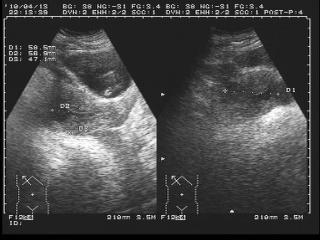

1、診斷方法:醫(yī)生會根據(jù)患者的病史、體征和輔助檢查來診斷宮外孕,常用的輔助檢查包括超聲檢查、血清人絨毛膜促性腺激素(hCG)測定等,醫(yī)生還會進(jìn)行詳細(xì)的婦科檢查以排除其他可能的疾病。